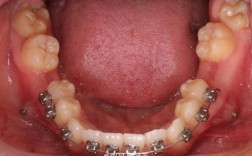

正畸模型测量是口腔正畸诊断与治疗设计中的核心环节,通过获取患者牙列、牙弓及咬合的精确数据,为制定个性化矫治方案提供客观依据,其测量内容涵盖牙冠形态、牙弓大小与形态、咬合关系、牙齿排列等多个维度,结合传统石膏模型与数字化扫描技术,实现对错牙合畸形的全面评估。

轴倾角与转矩:轴倾角为牙齿长轴与牙弓平面的夹角,反映牙齿近远中倾斜度;转矩为牙齿长轴与垂直于牙弓平面的夹角,反映唇舌/颊舌向倾斜度,传统模型需通过测量仪辅助判断,数字化模型可通过软件直接计算,二者共同评估牙齿在牙弓内的三维位置,指导弓丝弯制与托槽粘贴角度。

传统测量依赖游标卡尺、测量仪、石膏模型,而数字化扫描模型(如iTero、3Shape)通过三维成像实现数据自动采集与分析,精度达0.1mm,且可模拟牙齿移动、预测治疗效果,测量结果的临床意义在于:明确错牙合畸形机制(骨性/牙性)、制定个性化矫治方案(拔牙/非拔牙)、评估矫治中牙齿移动的可行性、预测治疗后稳定性。